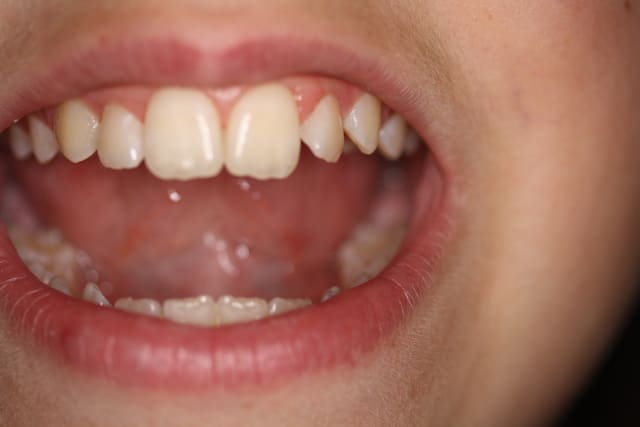

Je t envoie deux photos. Qu'en penses tu? Merci pour tes préceiux conseils

Photo damien dents 017 yunkol - Eugenol

Photo damien dents 019 pycbpi - Eugenol

L'image est floue, il n'y a pas assez de profondeur de champ : il faut donc fermer plus le diaphragme (F11 ou plus)

+1...f11 ou plus...et passer en mode manuel, avec sélection du SEUL collimateur central...là la mise au point se fait sur un collimateur périphérique....(le/les collimateurs utilisés sont en rouge lors de la map...et tu peux vérifier en modifiant les paramètres de lecture...tu peux faire afficher les collimateurs actifs...)...mais encore une fois...que le central pour la macro...